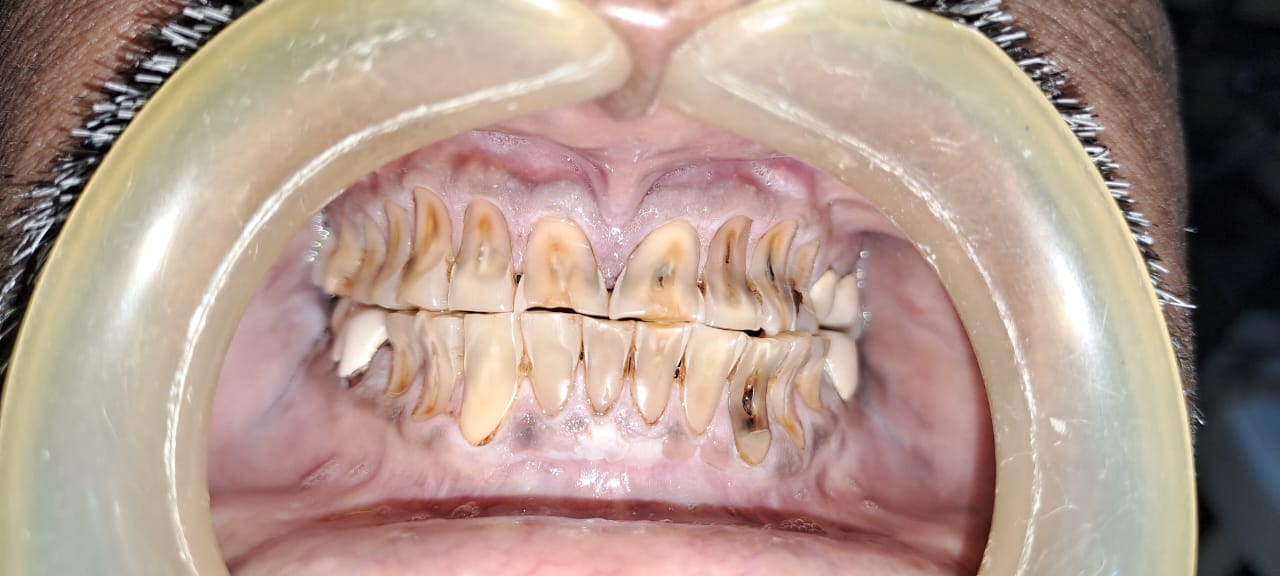

Patient wanted to get a new set of new teeth as old teeth were severely attrited and he was not able to chew. Medical history was taken and patient was fit for all the dental procedure. A detailed radiographic examination was conducted with the help of opg Treatment planning. A detailed case history along with radiological investigation and recording of of Bite of patient it was done in first visit. An appliance to relieve occlusion was given for 21 days Root canal treatment it was perform for all the teeth in subsequent visits. Occlusion was recorded using a specialised semi adjustable articulator. A temporary prosthesis was given to be used for or 15 days. A permanent Restoration was fabricated using pfm Crowns. A patience on patient end is a much needed thing as it involves time duration of of 1 to 2 months. Patient has to be absolutely serious about the treatment protocols which we are following as it involves use of appliances on patients end. Patient has to leave habit of eating Supari and tobacco as it was the cause in in severe reservation and attrition of teeth the artificial prosthesis is a finely crafted instrument that needs to be used with precision. so patients willingness and a positive mindset is Paramount in treating such cases.

Exciting News! Discover the Steps of Full Mouth Rehabilitation for a Dazzling Smile! Are parafunctional habits like kharra and ghutka taking a toll on your dentition? Say goodbye to improper chewing, loss of facial aesthetics, and digestive troubles with our expert team at Chintamani Dental Clinic!